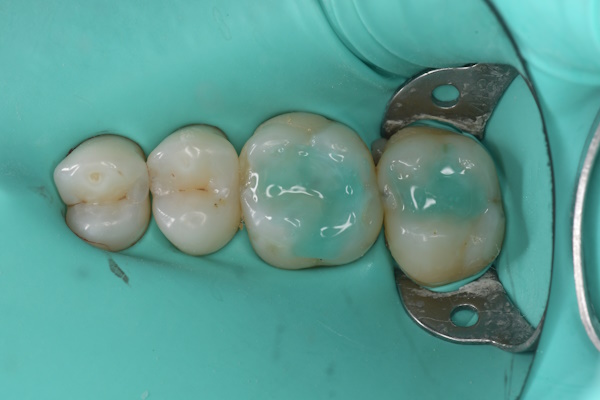

セラミック治療の治療例です。奥歯の虫歯を、見た目もきれいな材料で治したいとのご希望で来院されました。当院にて、2本同時にセラミック治療を行いました。接着効率を高めるため、ラバーダムを使用しています。オキシガードは、過酸化物と還元剤による化学重合反応により、歯科接着用レジンセメント表面の未重合層を硬化させる材料です。さらに、未重合層を空気から遮断することで、確実な硬化を促します。

術前から術後までの治療の流れ

オキシガード使用後